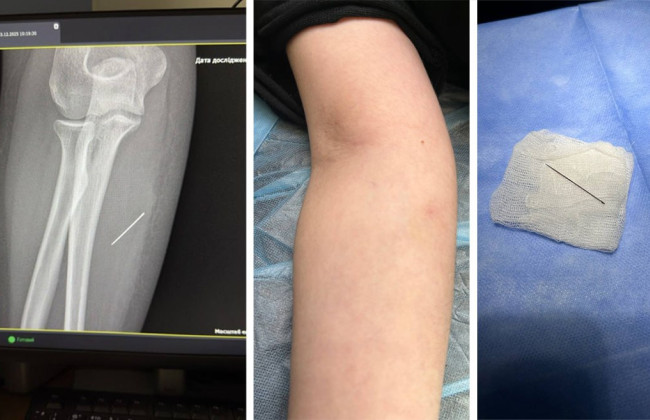

Під час огляду лікарі виявили ущільнення, біль від якого поширювався вглиб тканин. Дитину направили на УЗД м’яких тканин, де було зафіксовано сторонній предмет. Згодом рентген підтвердив, що голка зайшла під кутом 45 градусів і застрягла глибоко в м’язі. За тиждень вона просунулася ще далі.

Під час операції лікарі мали витягнути голку строго за траєкторією її входження, щоб уникнути ламання металу в тканинах. За допомогою рентген-навігації хірурги точно визначили місце розташування голки, виконали невеликий розріз і безпечно вилучили її.